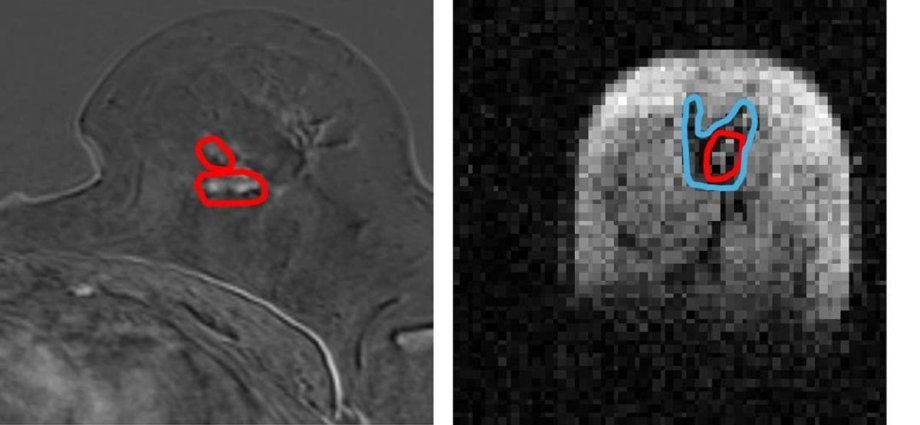

They found that the FCI scanner could distinguish tumour material from healthy tissue with more accuracy than current MRI methods.

The university described the scanner as “groundbreaking” and said it could identify “previously undetectable cancer tumour invasion”.

The Field Cycling Imager derives from MRI but can work at ultra-low magnetic fields which means it is capable of seeing how organs are affected by diseases in ways that were previously not possible, researchers said.

While similar to MRI in that MRI uses strong magnetic fields and radio waves to produce detailed images of the inside of the body without touching it, the FCI scanner can vary the strength of the magnetic field during the patient’s scan.

This means the FCI acts like multiple scanners in one and can extract multiple different types of information about the tissue.